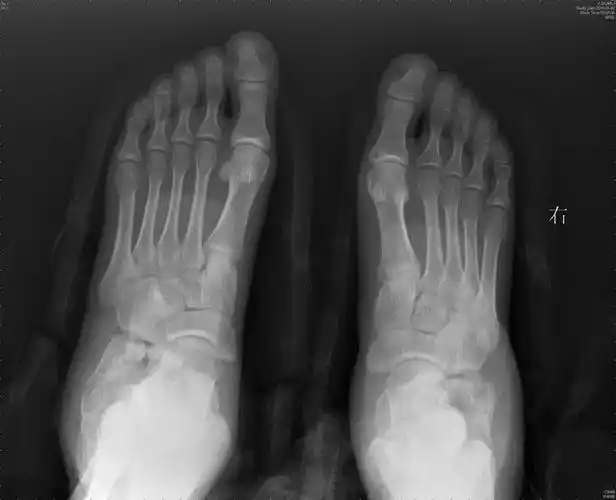

骨科基础跟骨骨折手术治疗的要点及技巧